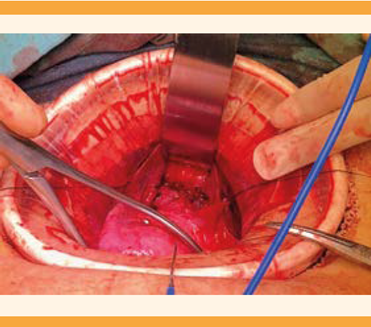

La laparotomía se practicó con incisión Pfannestiel y colocación de un separador tipo Alexis. Durante el procedimiento, el útero se encontró incrementado de tamaño, de 8 x 7 x 6 centímetros con finalización en fondo de saco ciego, múltiples adherencias laxas hacia el anexo izquierdo y colon sigmoides. Se procedió a liberar las adherencias útero-ováricas del fondo de saco e intestinales hasta lograr una adecuada movilidad uterina. Se procedió a la embrocación y colocación de un dilatador tipo Hegar en el canal vaginal como guía, que se palpó intrapélvico. Se identificó la distancia entre el fondo de saco ciego de la vagina y el útero de 1 centímetro. La comunicación entre el útero y la vagina se inició con la colocación de puntos de referencia en los extremos laterales de lo que se palpó como fondo de saco ciego de vagina (Figura 4). Se practicó una incisión y dejó a la vista el dilatador Hegar. Posteriormente se incidió en la parte baja del útero hasta exponer la cavidad endometrial; se obtuvo abundante líquido achocolatado proveniente de la ematómetra. Se terminó la evacuación y procedió a la aplicación de puntos simples en los bordes de la incisión uterina; en todos sus extremos se hizo un orleado para evitar tomar tejido endometrial. Se comenzó la unión del neo-cérvix con el canal vaginal y alrededor de toda la estructura y antes del cierre completo se aplicaron puntos simples con vicryl, se ferulizó la comunicación con una sonda Foley 22 (Figura 5) que permaneció durante cinco semanas posteriores a la cirugía. Se finalizó el cierre de la estructura (Figura 6), se verificó la adecuada hemostasia y se procedió al cierre de la pared abdominal.

Figura 5 Aplicación de una sonda Foley 22 para mantener permeable la comunicación entre la vagina y el útero.